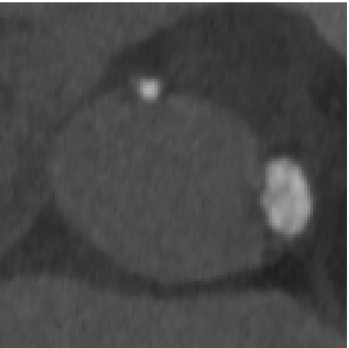

FEops评估冠脉风险

瓣膜植入前的主动脉根部形态

瓣膜植入后的主动脉根部形态

根据FEops报告上的左右冠脉CT截面得知RCA Height:12.0mm、LCA Height:12.0mm,具有一定冠脉闭塞风险,通过观察模拟植入后瓣叶与冠脉开口的位置关系,得知该患者冠脉闭塞风险比较高,建议行冠脉保护确保手术安全。